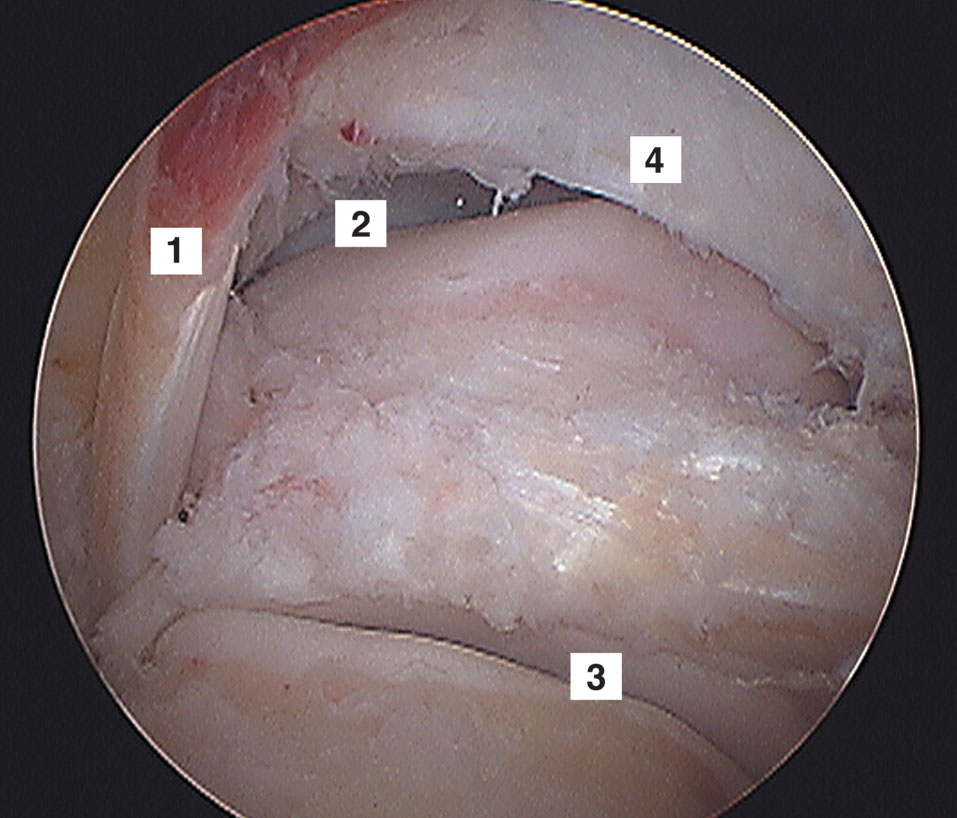

Figura 4: Vista artroscópica de 1) Flexor largo del hallux,

2) Articulación tibioastragalina, 3) Articulación subastragalina

y 4) Ligamento transverso.

Las superficies articulares que podemos ver en la artroscopia posterior son: tibia distal, ambos maléolos, astrágalo (superior, inferior y ambos lados) y cara superior del calcáneo. Que forman las articulaciones tibioastragalina y subastragalina. Para identificar una articulación de otra por artroscopía es útil realizar flexoextención y rotaciones de tobillo. Si se moviliza la articulación cuando realizamos flexoextención estamos en presencia de la articulación tibioastragalina y si se moviliza con rotaciones estamos en presencia de la subastragalina.

Luego se puede identificar el proceso lateral del astrágalo, cápsula y ligamentos posteriores, tendón del tibial posterior, tendones peróneos, articulación tibioastragalina

y articulación subastragalina (Fig. 13).